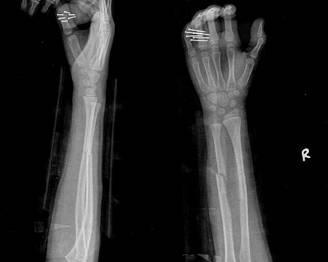

經(jīng)過醫(yī)生的診斷,小明被確診為尺橈骨融合,這是一種骨骼疾病,會導致尺骨和橈骨無法正?;顒?,聽到這個消息后,小明和他的朋友們都感到有些緊張和害怕,但他們并沒有放棄,而是選擇相互鼓勵,共同面對這個挑戰(zhàn)。

在醫(yī)生的介紹下,他們了解到了一種最新的尺橈骨融合治療方法——通過微創(chuàng)手術(shù)進行骨骼融合的新技術(shù),這種方法不僅減少了手術(shù)風險,還能更快地恢復活動能力,雖然小明感到害怕,但他的朋友們一直陪伴在他身邊,給予他勇氣和力量。